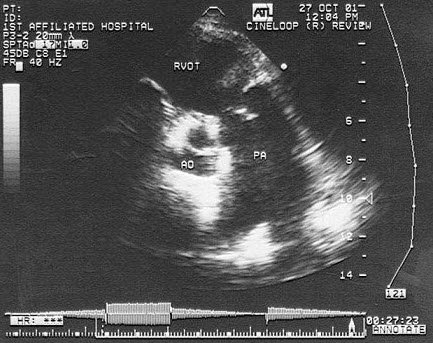

30、单项选择题

根据心尖四腔切面声像图所示,超声诊断为()

56、单项选择题 该肺动脉狭窄最可能为哪一型()

A.肺动脉闭锁

B.肺动脉瓣狭窄

C.肺动脉瓣下狭窄

D.肺动脉瓣上狭窄

E.肺动脉扩张